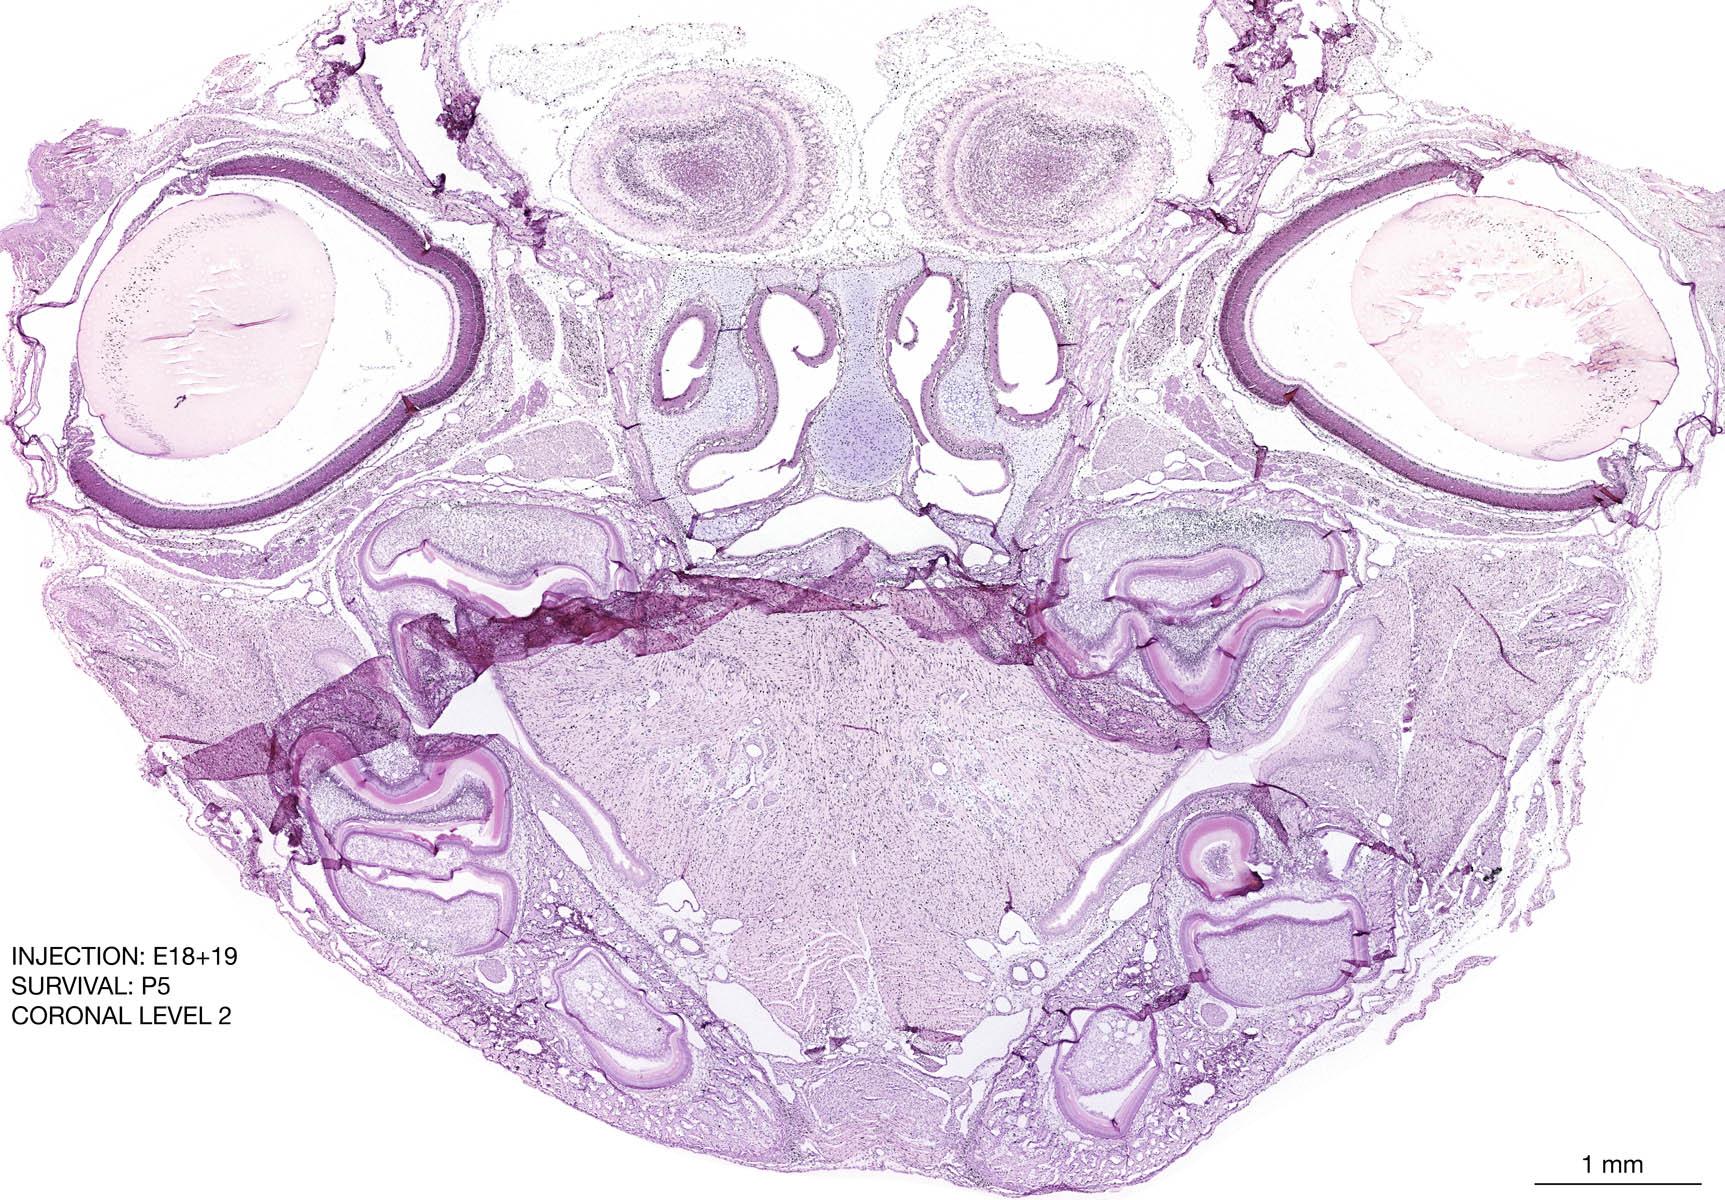

The images below are from the brain of a rat that was exposed to tritiated thymidine on E18+19 and survived to P5. Download: Large | High Res Download: Large | High Res Download: Large | High Res Download: Large | High Res Download: Large | High Res Download: Large | High Res Download: Large | High Res Download: Large | High Res Download: Large | High Res Download: Large | High Res Download: Large | High Res Download: Large | High Res Download: Large | High Res Download: Large | High Res Download: Large | High Res Download: Large | High Res Download: Large | High Res Download: Large | High Res Download: Large | High Res Download: Large | High Res Download: Large | High Res Download: Large | High Res Download: Large | High Res Download: Large | High Res